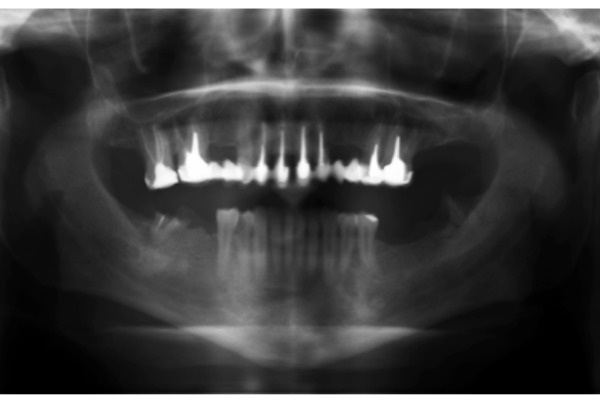

Periapical Microsurgery: An alternative in the treatment of persistent apical periodontitis: 2 case reports

Leer artículo

Conservative approach in a patient with multiple radiolucent periapical lesions using endodontics and surgery